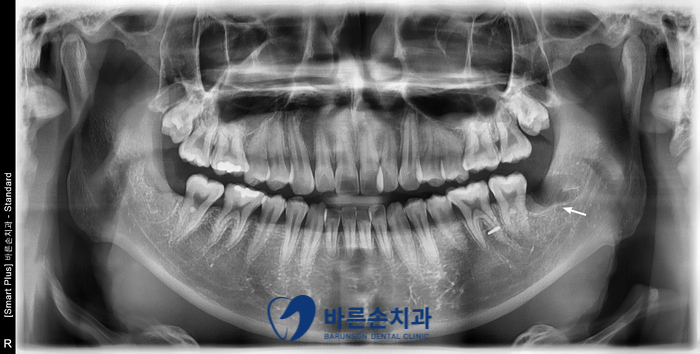

안녕하세요. <의정부 바른손치과>입니다.! 오늘은 사랑니 발치 증례를 보여드리도록 하겠습니다. 이 환자분은 20대 중반의 남성분으로 양쪽 아래 사랑니가 아프셔서 발치를 하러 저희 바른손치과를 찾아주셨습니다. 엑스레이 사진에서 보시면 양쪽 위 아래 사랑니가 모두 있고 왼쪽 아래 사랑니가 누워서 부분적으로 매복되어 있는 상태입니다. 구강 내 사진입니다. 좌우 모두 사랑니 머리가 일부만 구강내로 맹출해있습니다. 이런 경우 음식물이 끼기 쉽고, 칫솔로 제거도 쉽지가 않습니다. 그래서, 잇몸이 부어 피가 나고 아픈 경우가 자주 일어 날 수 있고 나아가 앞에 있는 치아 까지 썩게 할 수 있습니다ㅜㅜ 이런 경우엔 사랑니 발치를 통해 구강 환경 개선을 해야합니다!!! 사랑니 발치에 앞서 3D CT 촬영을 하였습니다. 사랑니의 형태와 위치, 아래턱뼈에 있는 하치조신경관의 해부학적 위치를 정확히 확인 후 발치에 들어갑니다. 오른쪽 아래 사랑니를 발치하고 엑스레이를 찍어 확인하였습니다. 왼쪽아래 옆으로 누워있는 사랑니도 발치를 하였습니다. 환자분께서는 문제를 일으키던 사랑니를 뽑으니 홀가분하고 시원하다고 하셨습니다.!! 약 일주일 정도 회복기간을 가지시면 사랑니 부위의 잇몸은 어느정도 아물게 됩니다. 사랑니 발치 더이상 두려워 하지 마시고 <의정부 바른손치과>에서 뽑으세요^^ |